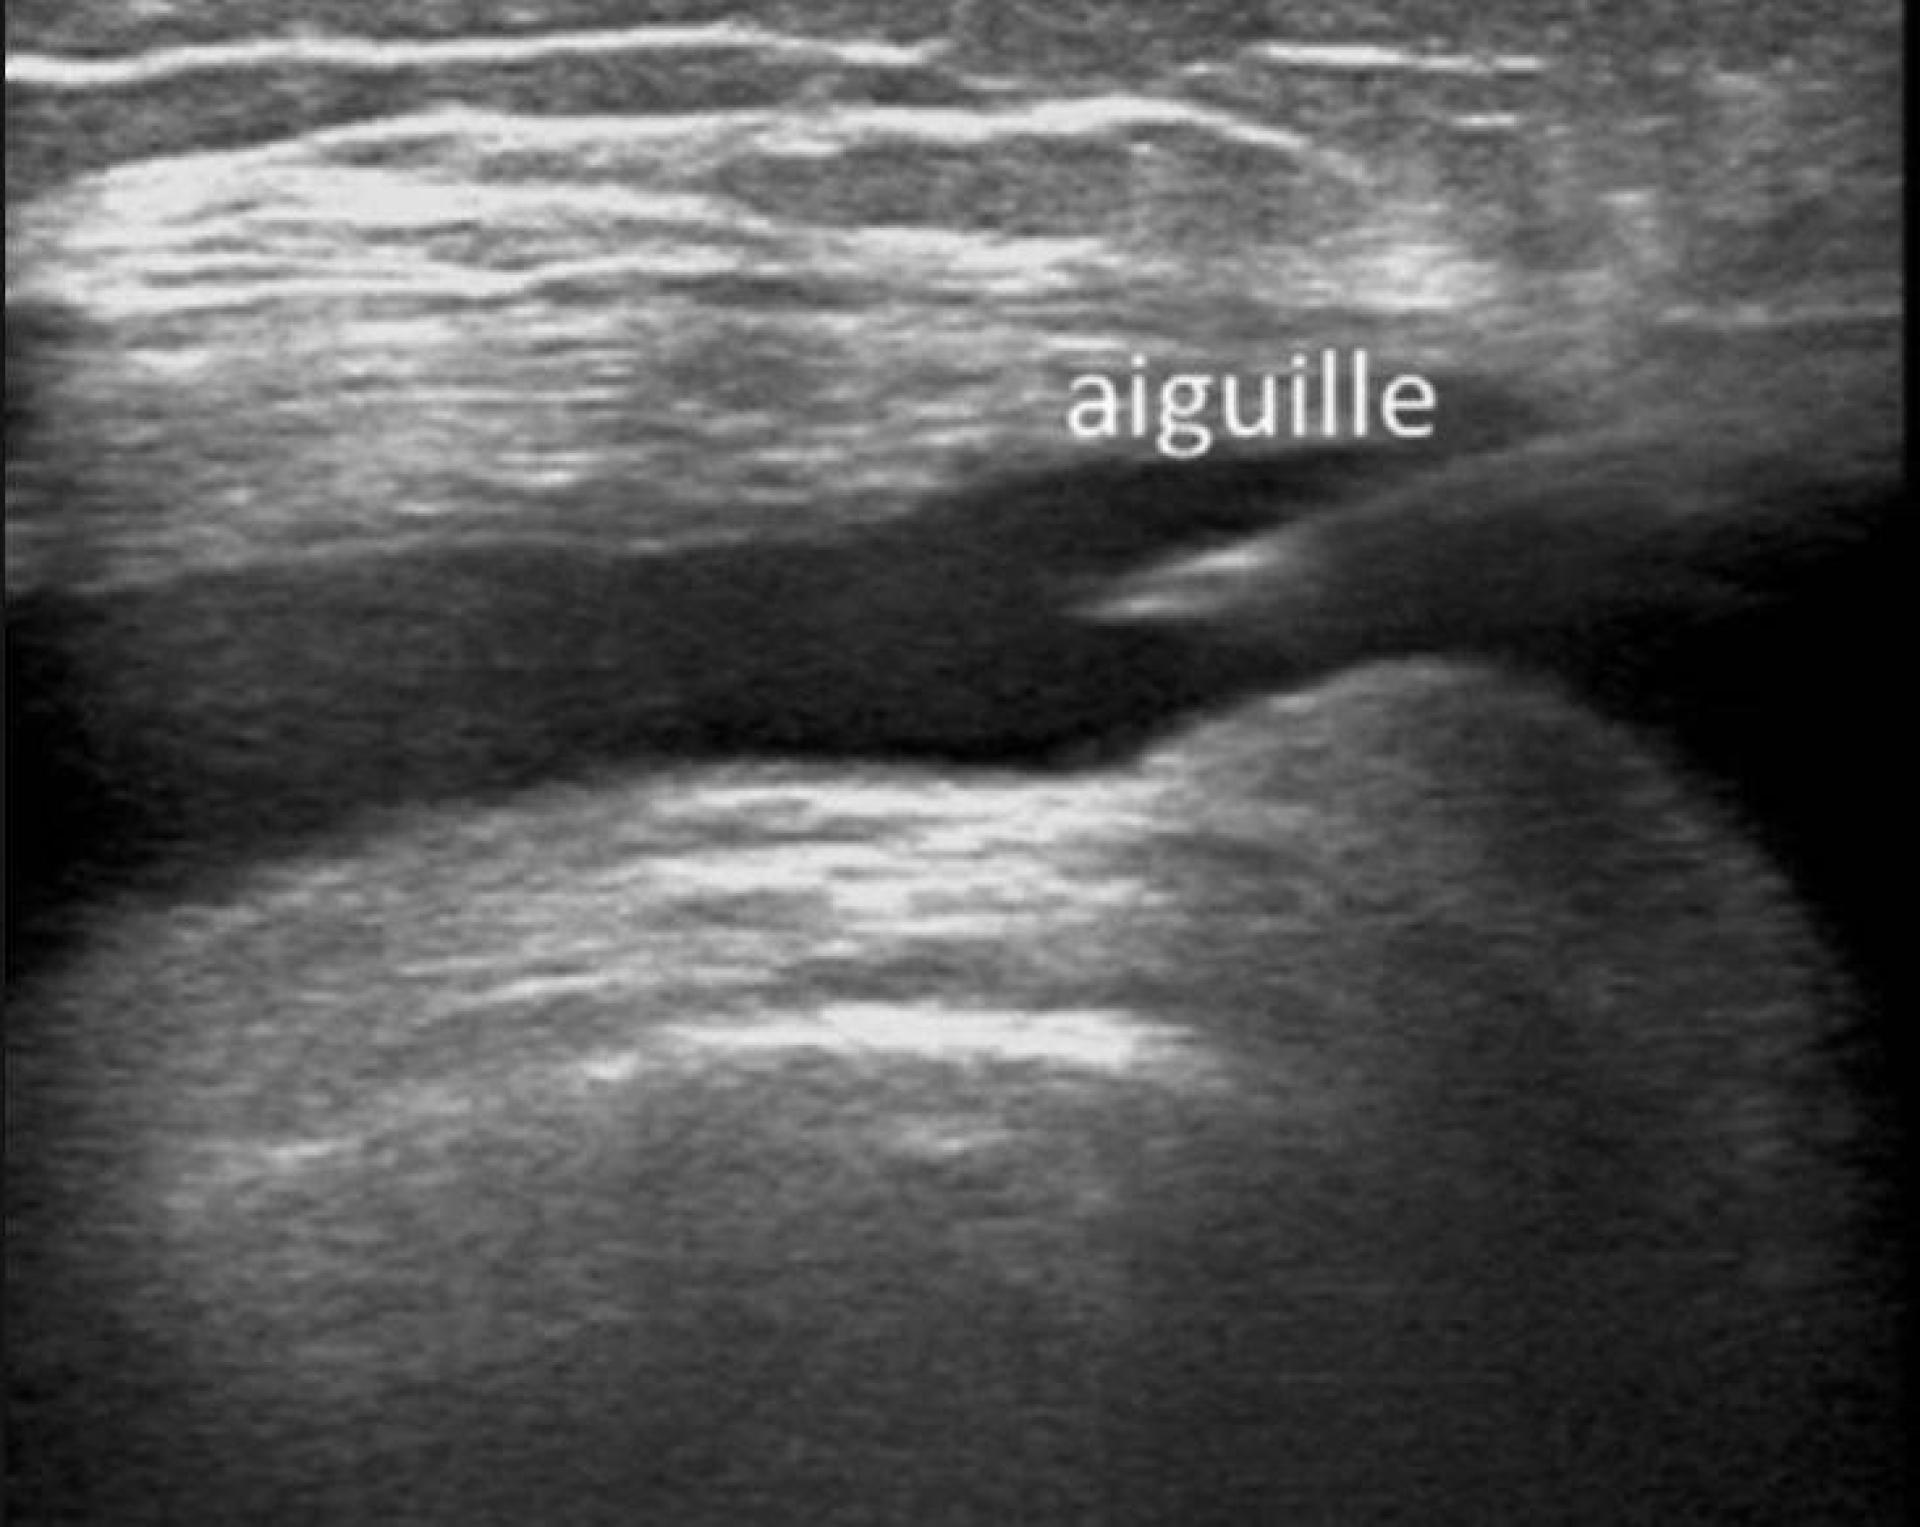

Faire une infiltration sous guidage échographique

L'injection d'un corticoïde dans une articulation, au niveau d'une bourse de glissement ou au contact d'un tendon est communément appelée "infiltration".Nous réalisons ce geste avec un guidage échographique afin d'injecter au mieux le médicament cortisonique.L'infiltration peut être couplée avec u...